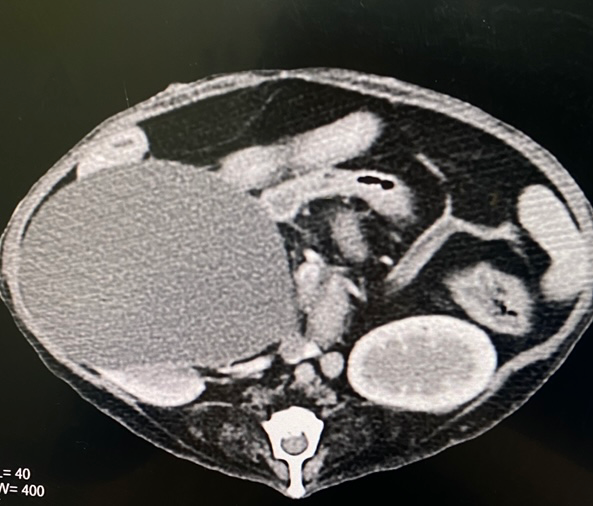

첨부해주신 CT 영상을 볼때 낭성 변화를 보이는 신장의 실질에 종영이 반대편 신장과 거의 유사한 수준으로 보이고 있어

낭성으로 구조 변화를 보이고 있으나 신장의 기능은 유지되고 있을 가능성이 높습니다.

한쪽을 적출한것만으로도 남겨진 신장의 능력이 100% 보전되어 있는 상태더라도 이 친구의 신장 능력은 50%로 감소한 상태입니다.

즉, 아무리 남겨진 신장이 100%의 능력을 가지고 있더라도 만성 신부전 상태로 가정해야 합니다.